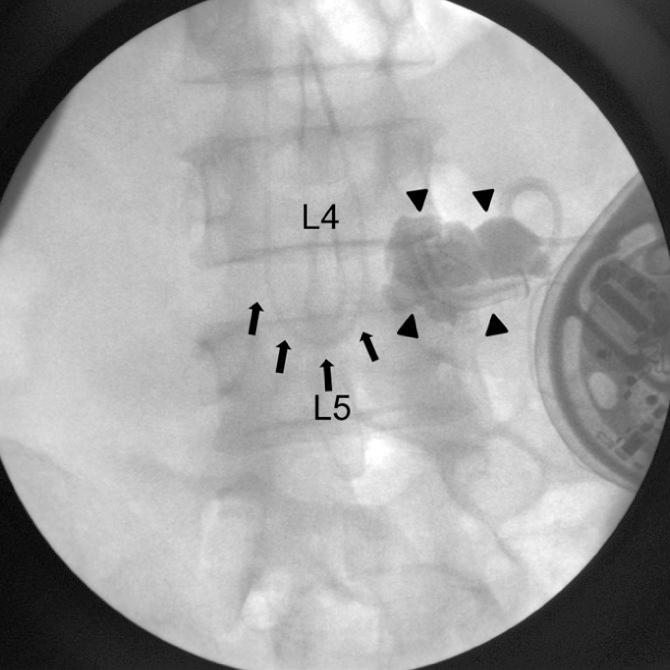

An intrathecally located broken catheter used for an intrathecal drug delivery system.

The intrathecal drug delivery system (ITDDS), an effective treatment tool for intractable spasticity and pain, is associated with various complications but breakage of the catheter is rare. We report the case of a 50-yr-old man with ITDDS, in whom an intrathecal catheter was severed, resulting in a 28.6-cm-long intrathecal fragment. The catheter completely retracted into the intrathecal space from the anchor site. The catheter was severed during spine flexion, and the total distal fragment was repositioned in the intrathecal space. Although the outcome of ITDDS was associated with the length or diameter of the broken catheter, no neurologic complications occurred in our patient. Thus, we inserted another catheter instead of removing the old one. Thereafter, the patient has been regularly followed up, and no neurologic complications have developed during the 28 months.